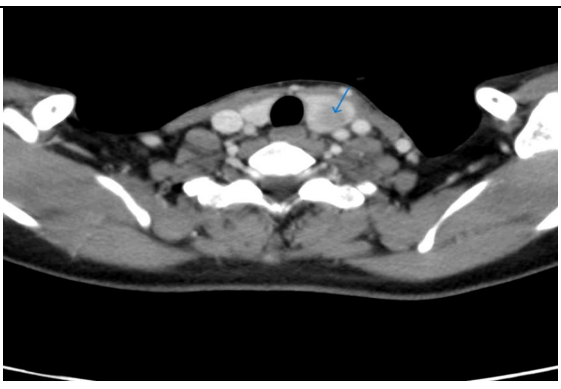

A 38 year old female presented with the complaints of pain and difficulty during swallowing and history of weight loss. Up on examination, a swelling was noted on the left side of her neck, which moved with deglutition. Ultrasound (USG) revealed a well circumscribed hypoechoic nodule measuring 3.2x2.1cm in the left lobe of thyroid with no extrathyroidal extension, however the nodule was compressing the esophagus. Fine needle aspiration was performed on the lesion and stained with Papanicolaou (PAP) stain and May Grunwald Geimsa (MGG) stains. The smears exhibited high cellularity with globoid clusters and three dimensional tissue fragments composed of aggregates of cells with central core of homogenous basement membrane material with cells having basaloid morphology and scant cytoplasm (Figure 2). MGG smears highlighted pink/ magenta amorphous basement membrane hyaline globules in the clusters of tumor cells (Figure 3). Cell block preparation of fine needle aspiration showed cribriform pattern of tumor cells with hyaline globules (Figure 4). Immunocytochemistry conducted on cell block shows TTF-1 positivity in normal thyroid follicles and negative staining in tumor cell clusters. CD117 and synaptophysin were inconclusive on cell block, but based on morphology this case was reported as adenoid cystic carcinoma of thyroid. Contrast-enhanced computed tomography (CECT) prior to surgery depicted a well defined heterogeneously enhancing hypodense lesion in the left lobe of thyroid measuring 3.2x2.1x1.7cm with no  additional lesions or abnormalities noted in the adjacent structures like trachea, larynx, oesophagus or upper mediastinum(Figure 1).  The excised left hemi-thyroidectomy specimen was received which showed a grey white solid homogenous lesion measuring 3.5x2.2x2cm reaching till the capsule. No cystic spaces/papillary projections/colloid seen in the lesion grossly. Adjacent thyroid parenchyma was normal. Histopathology sections showed tumor arranged in tubules and cribriform pattern along with hyaline globules suggesting the diagnosis of adenoid cystic carcinoma of thyroid, limited to thyroid without extra thyroid extension (Figure 5). IHC with CD117 showed cytoplasmic positivity in tumor cells further supporting the diagnosis (Figure 6).

Figure 5: H & E section from Left hemithyroidectomy specimen (20x) show well circumscribed tumor with features of adenoid cystic carcinoma, limited to thyroid with adjacent normal thyroid parenchyma (Arrow marks the junction of tumor with normal thyroid parenchyma).